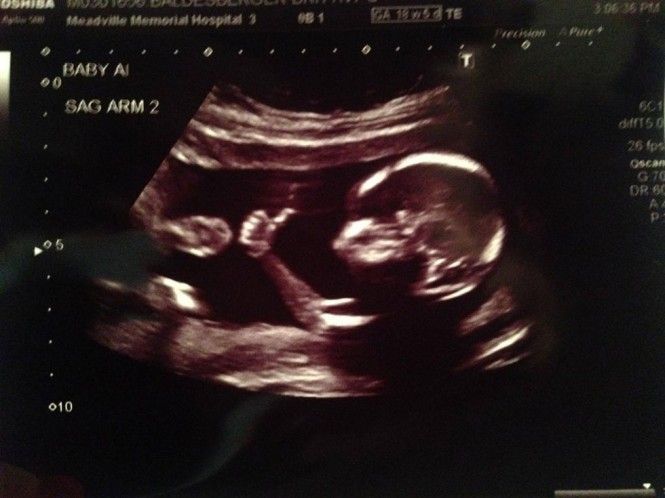

Ένα έμβρυο όπως φαίνεται στο υπερηχογράφημα που έφερε στο φως της δημοσιότητας ο πατέρας του, με τον αντίχειρά του κάνει like!

Η συγκεκριμένη φωτογραφία έχει σπάσει κάθε ρεκόρ κοινοποιήσεων στα social media και κάποιοι αναρωτιούνται αν έχει υποστεί photoshop. Ο πατέρας του εμβρύου πάντως αφού διοχεύτευσε την συγκεκριμένη φωτογραφία στο διαδίκτυο επιμένει ότι το μωρό του έχει στενή σχέση με το…διαδίκτυο από την κοιλιά της μητέρας του! Δείτε την φωτογραφία που έχει εκατομμύρια likes σε όλον τον κόσμο: